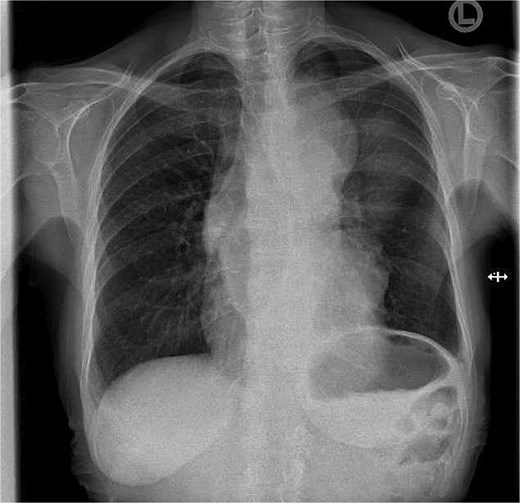

A 71-year-old female presented to her general practitioner with unintentional weight loss of 30 kg over the course of 6 months. She denied any further complaints. Her medical history included arterial hypertension and type II diabetes mellitus with no previous oncological history. Clinical examination revealed a cachectic patient without other relevant findings. A chest X-ray was performed as the initial imaging study, which showed an enlarged mediastinum (Fig. 1). In the case of a suspected mediastinal tumor, a chest CT scan was conducted and confirmed the presence of a 11.4 × 9.2 cm mediastinal tumor in the anterior mediastinum (Fig. 2). CT imaging revealed, in addition to the infiltration of the chest wall, a very close relationship with the aortic arch and the left subclavian artery. Further evaluation took place at a local hospital. First, an endobronchial ultrasound with transbronchial needle aspiration (EBUS-TBNA) of left paratracheal tumor mass revealed a B2 thymoma. Staging was completed with magnetic resonance tomography (MRI) of the brain, which excluded cerebral metastases. Due to suspicion of infiltration of the aorta, a complementary MRI of the mediastinum was performed but provided no additional information. The case was presented at a multidisciplinary tumor board in the presence of thoracic surgeons. The tumor was deemed inoperable and treated with four cycles of carboplatin and paclitaxel. At restaging, definitive radiotherapy was recommended. The patient sought a second opinion in our department. Re-staging with CT showed stable disease. The tumor was suspected to invade the sternum, left 1st to 3rd ribs, pericardium, and left upper lobe. Infiltration of the aorta appeared unlikely but could not be completely excluded.

Chest X-ray at first presentation showing an enlarged mediastinum.